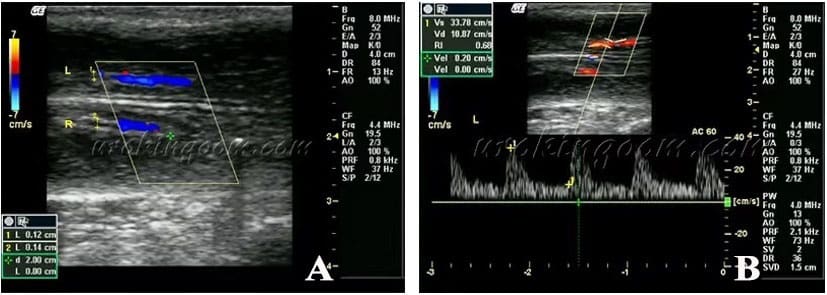

陰莖彩色都卜勒超音波檢查(Color duplex Doppler ultrasonography (CDDU)

超音波是利用聲波來產生軟組織的影像。高階的陰莖彩色都卜勒超音波檢查可以測量陰莖及血管周徑,並評估陰莖白膜、硬結及鈣化程度、海綿體纖維化等情形(圖1A)。陰莖彩色都卜勒超音波檢查特別用於評估觀察陰莖勃起功能,測量陰莖的血流參數,了解動脈血流情形,是否存在有陰莖動脈灌流不足造成動脈性勃起功能障礙、或陰莖靜脈滲漏性勃起功能障礙等問題(圖1B)。